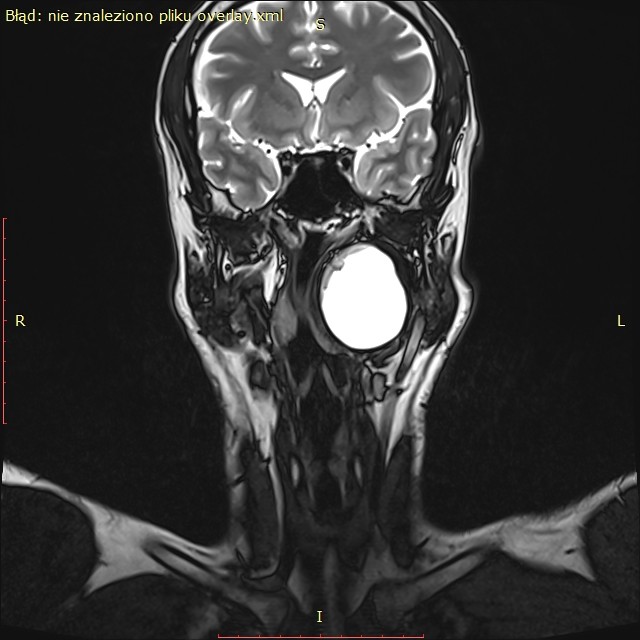

Badanie rezonansu magnetycznego wykazało (widoczne na zdjęciu) u pacjenta obecność dużej zmiany torbielowatej w przestrzeni przygardłowej po stronie lewej o wymiarach 54x42x38 mm. Zmiana miała postać torbieli zawierającej jednolity płyn, z pogrubiałą, postrzępioną wewnętrzną ścianą i gładką powierzchnią zewnętrzną. Torbiel powodowała przemieszczenie i ucisk okolicznych struktur. Biopsja aspiracyjna cienkoigłowa sugerowała torbiel boczną szyi.